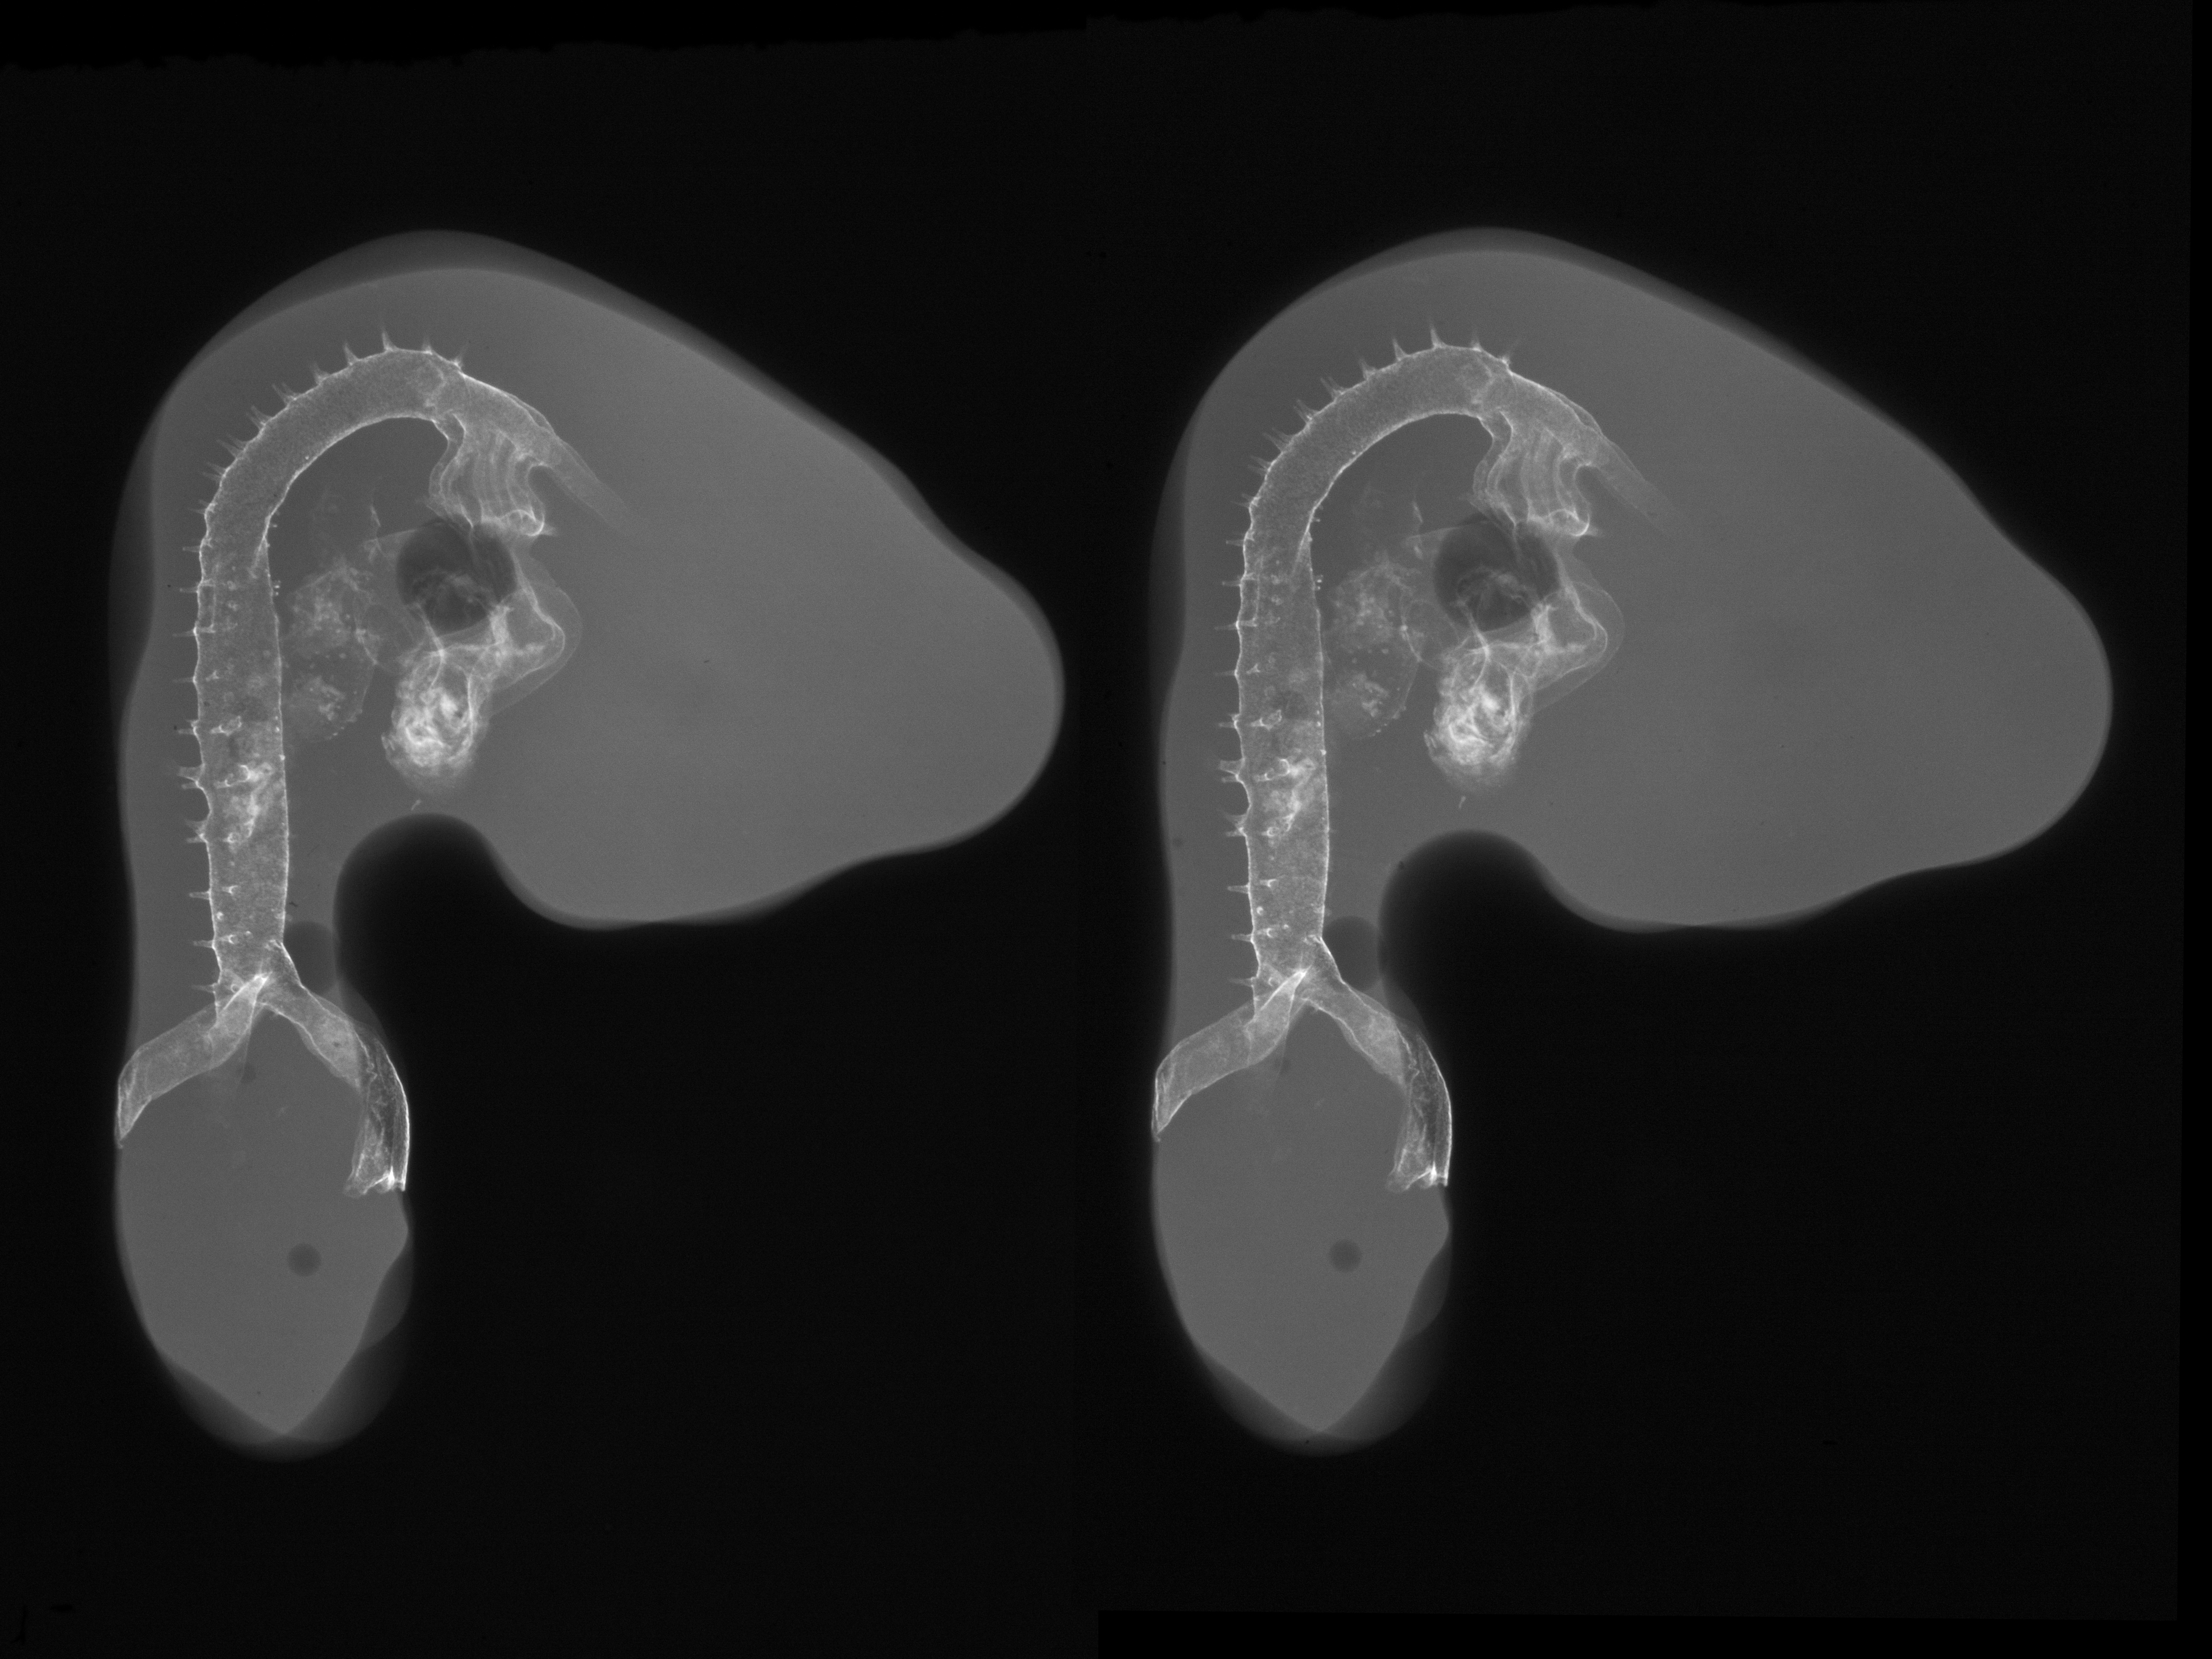

Chick Embryo Microangiography

Hamburger-Hamilton (HH) Stage 21 (approx. 3.5 days)

Stereo X-Ray Micrographs